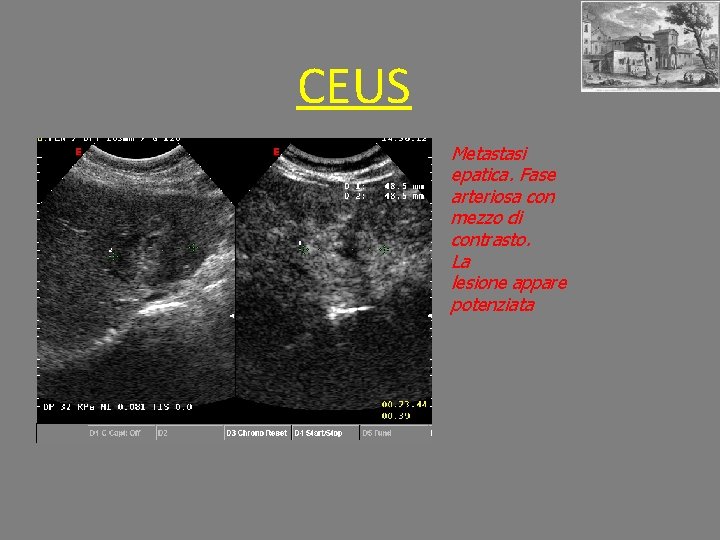

CEUS Metastasi epatica. Fase arteriosa con mezzo di contrasto. La lesione appare potenziata